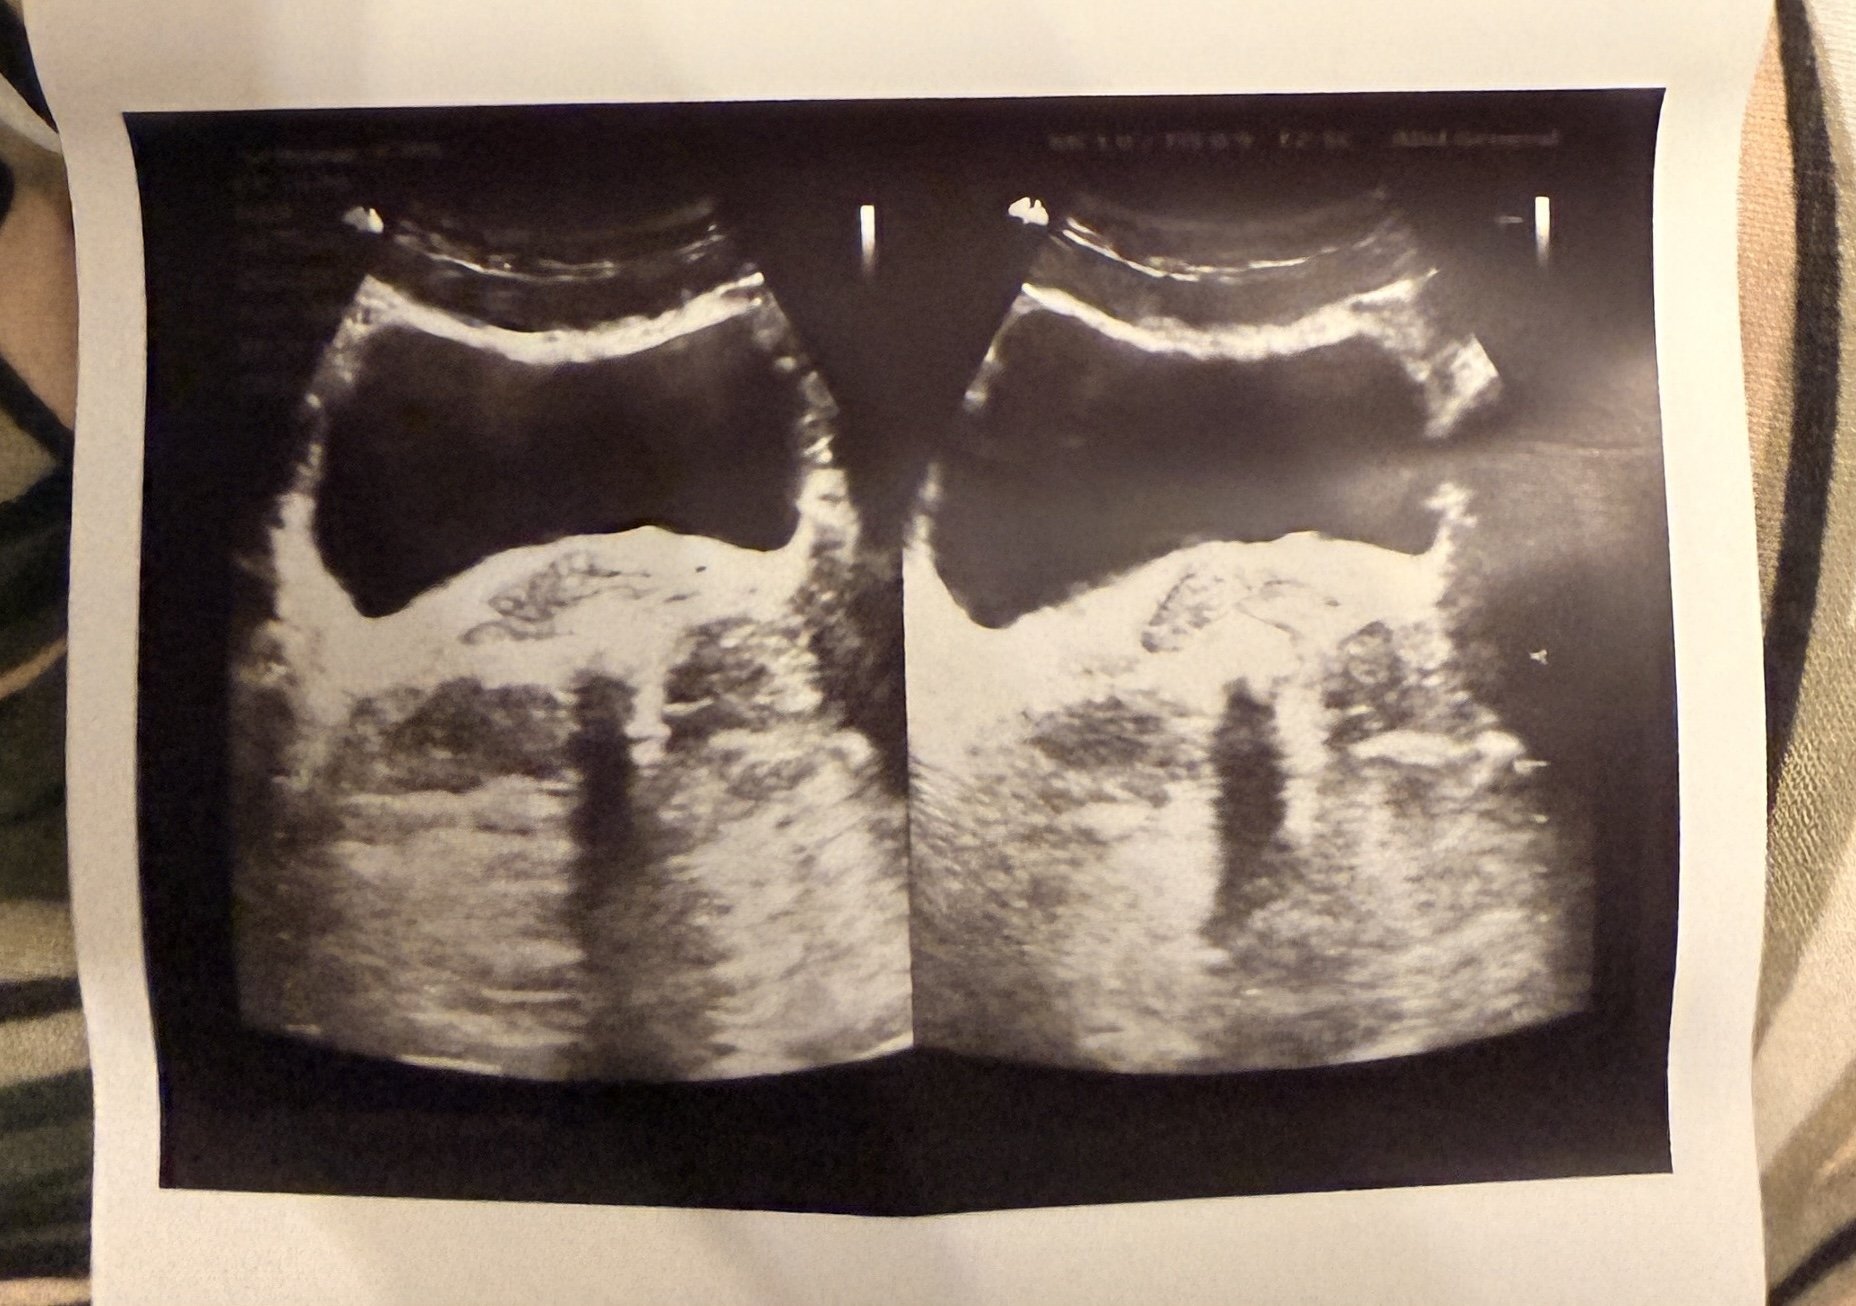

Здравейте! Не видях скорошна тема по въпроса, затова реших да създам нова. Моля ако има хора, които са прескочили тази ужасна “диагноза” да споделят опита си. Жена на 26год. съм, всичко започна след една много лоша настинка на 19 Декември. Първо се появи леко по учестено уриниране, посетих уролог, който ме претупа само с Монурал и каза , че най-вероятно е цистит и ако не мине от Монурала да си пусна стерилна урина. Както очаквах, не мина, а резултатите бяха чисти. За няколко дни прогресира до неконтролируемо уриниране на всеки 3-4 минути през цялата нощ, като вече след всяко ходене по малка нужда тялото ми се тресеше, а аз вече бях на ръба да полудея ( който не е минал през това, не знае до каква лудост може да те докара) . След това реших да потърся друг уролог (гр.Варна) . Като той ми каза, че това за него е свръхактивен пикочен мехур. Изписа ми Цефиксим и Везизол 5мг. Вече пишкам максимум до 10 пъти на ден, но това усещане не се повлиява- имам чувството че като си докосна корема ниско долу си пипам мехура- супер чувствителен е , усещам гъделичкане сякаш мехура е. пълен, доста често получавам нещо като спазъм на мехура, сякаш ще се напишкам, след това ме отпуска. Дори при движение на червата или когато имам газове, усещам притискане на мехураа, когато сядам усещам натиск от ануса към мехура, а като вървя все едно ми се тресе мехура и го усещам пълен. Имам чувството че съм в някакъв омагьосан кръг и не знам какво да правя. Никой не обръща достатъчно внимание на проблема, а това за мен не е нормално и трябва да се търси първоизточника на проблема.. Прикачвам снимка от ехографа си също.